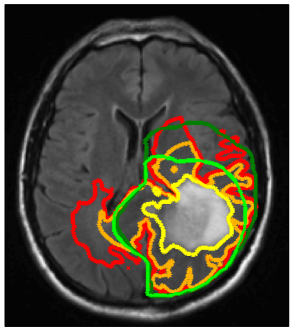

Refer to caption

Figure 6: Comparison of dose distributions (in units of Gy): (a) for a plan based on manual target volumes; (b) for model-derived target volumes. The difference of the dose distribution is shown in (c). Figure (d) shows the planned dose distribution for the 3D conformal plan the patient was treated with.

Figure 6 shows the dose distributions obtained for two treatment plans. The plan in figure 6a is based on the manually drawn target volumes, whereas the plan in figure 6b is based on the target volumes derived from the growth model. For the sake of comparison, the plan based on model-derived targets was optimized by imposing an additional constraint on the integral dose delivered to the patient, i.e. we minimize objective function (6-8) subject to the constraint

where V𝑉V denotes the set of all voxels in the patient, and dintsuperscript𝑑𝑖𝑛𝑡d^{int} denotes the integral dose obtained for the treatment plan based on the manual target volumes. Figure 6c shows the difference of the plans in figures 6a and 6b. It can be seen that in plan 6b more dose is delivered to the contralateral hemisphere. Under the constraint that integral dose is not increased, this is compensated for by delivering less dose to other regions, e.g. near the lateral sulcus.

To quantify the difference in dose distributions in figure 6, we calculate the Dice coefficients for the volumes enclosed by selective isodose lines. The Dice coefficients for the 57 Gy and the 46 Gy isodose line evaluate to 0.84 and 0.83, respectively. In section 3.4 we calculated the Dice coefficient between manual and model-derived boost and CTV volumes, which are 0.78 and 0.77, respectively. It is apparent that differences in target volumes only partly translate into differences in dose distributions. The rugged shape of the model-derived target volume that arises from reduced infiltration of gray matter is mostly not of relevance for radiotherapy planning. Due to the physical characteristics of photon beams it is not possible to spare thin layers of gray matter surrounding small fissures.